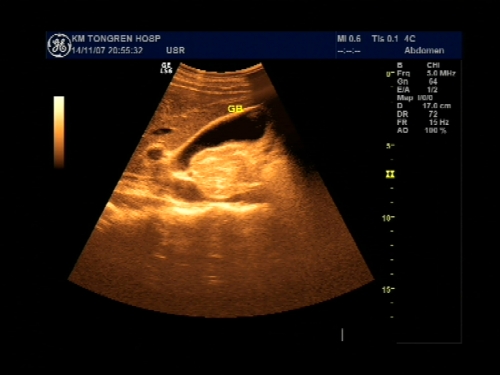

超声声像图能显示肝脏切面形态、大小、肝内实质结构、管道系统及肝周邻,并能根据肝内管道系统区分肝脏各叶、各段,对病变进行定位诊断。彩色多普勒超声能显示肝脏的血流,并能对肝脏的血流动力学参数进行测定,不仅能诊断肝脏的血管病变,还能了解正常肝脏及病变肝脏的血供及回流状态,目前已成为临床诊断肝脏疾病的常规检查方法。

彩色多普勒超声扫查

彩色多普勒能量图